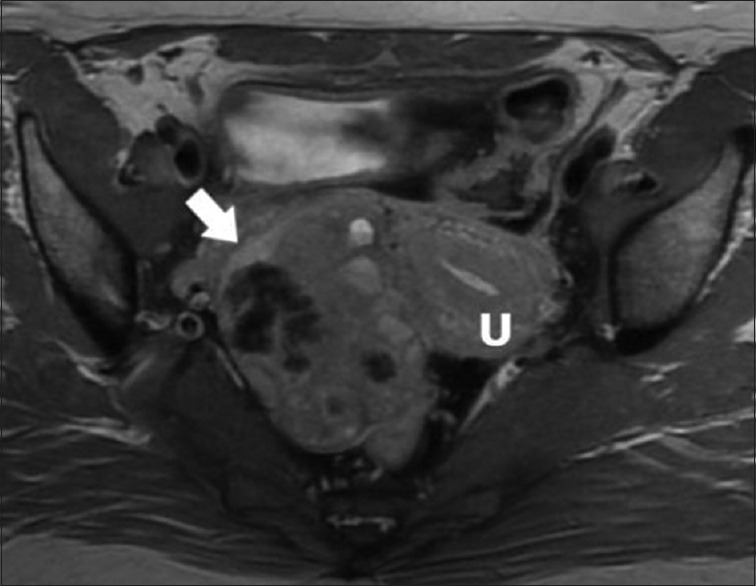

We report a case of a pedunculated adenomyoma with osseous metaplasia, which mimics a dermoid cyst on magnetic resonance imaging (MRI) making it a considerable differential diagnosis. A 40-year-old female presented with chronic lower abdomen pain for a year. Pelvic MRI revealed a right-sided pelvic mass measuring 8.4 cm × 5.7 cm. The mass appeared isointense, with hyperintense contents similar to calcifications and fatty content. These results strongly indicated a dermoid cyst. During laparoscopy, a massive pedunculated uterine myoma was seen on the right posterior-fundal part of the uterus. During laparoscopic myomectomy, calcified tissues were discovered during manual morcellation. The histopathological examination confirmed the diagnosis of adenomyoma with widespread calcification and localized osseous metaplasia. Osseous metaplasia is an uncommon cytomorphological transformation seen mostly in the endometrium. Adenomyomas are rare, benign uterine tumors that are frequently misdiagnosed. In this case, the preoperative diagnosis suggested a dermoid cyst, broadening the differential diagnosis for calcified uterine tumors detected on MRI.